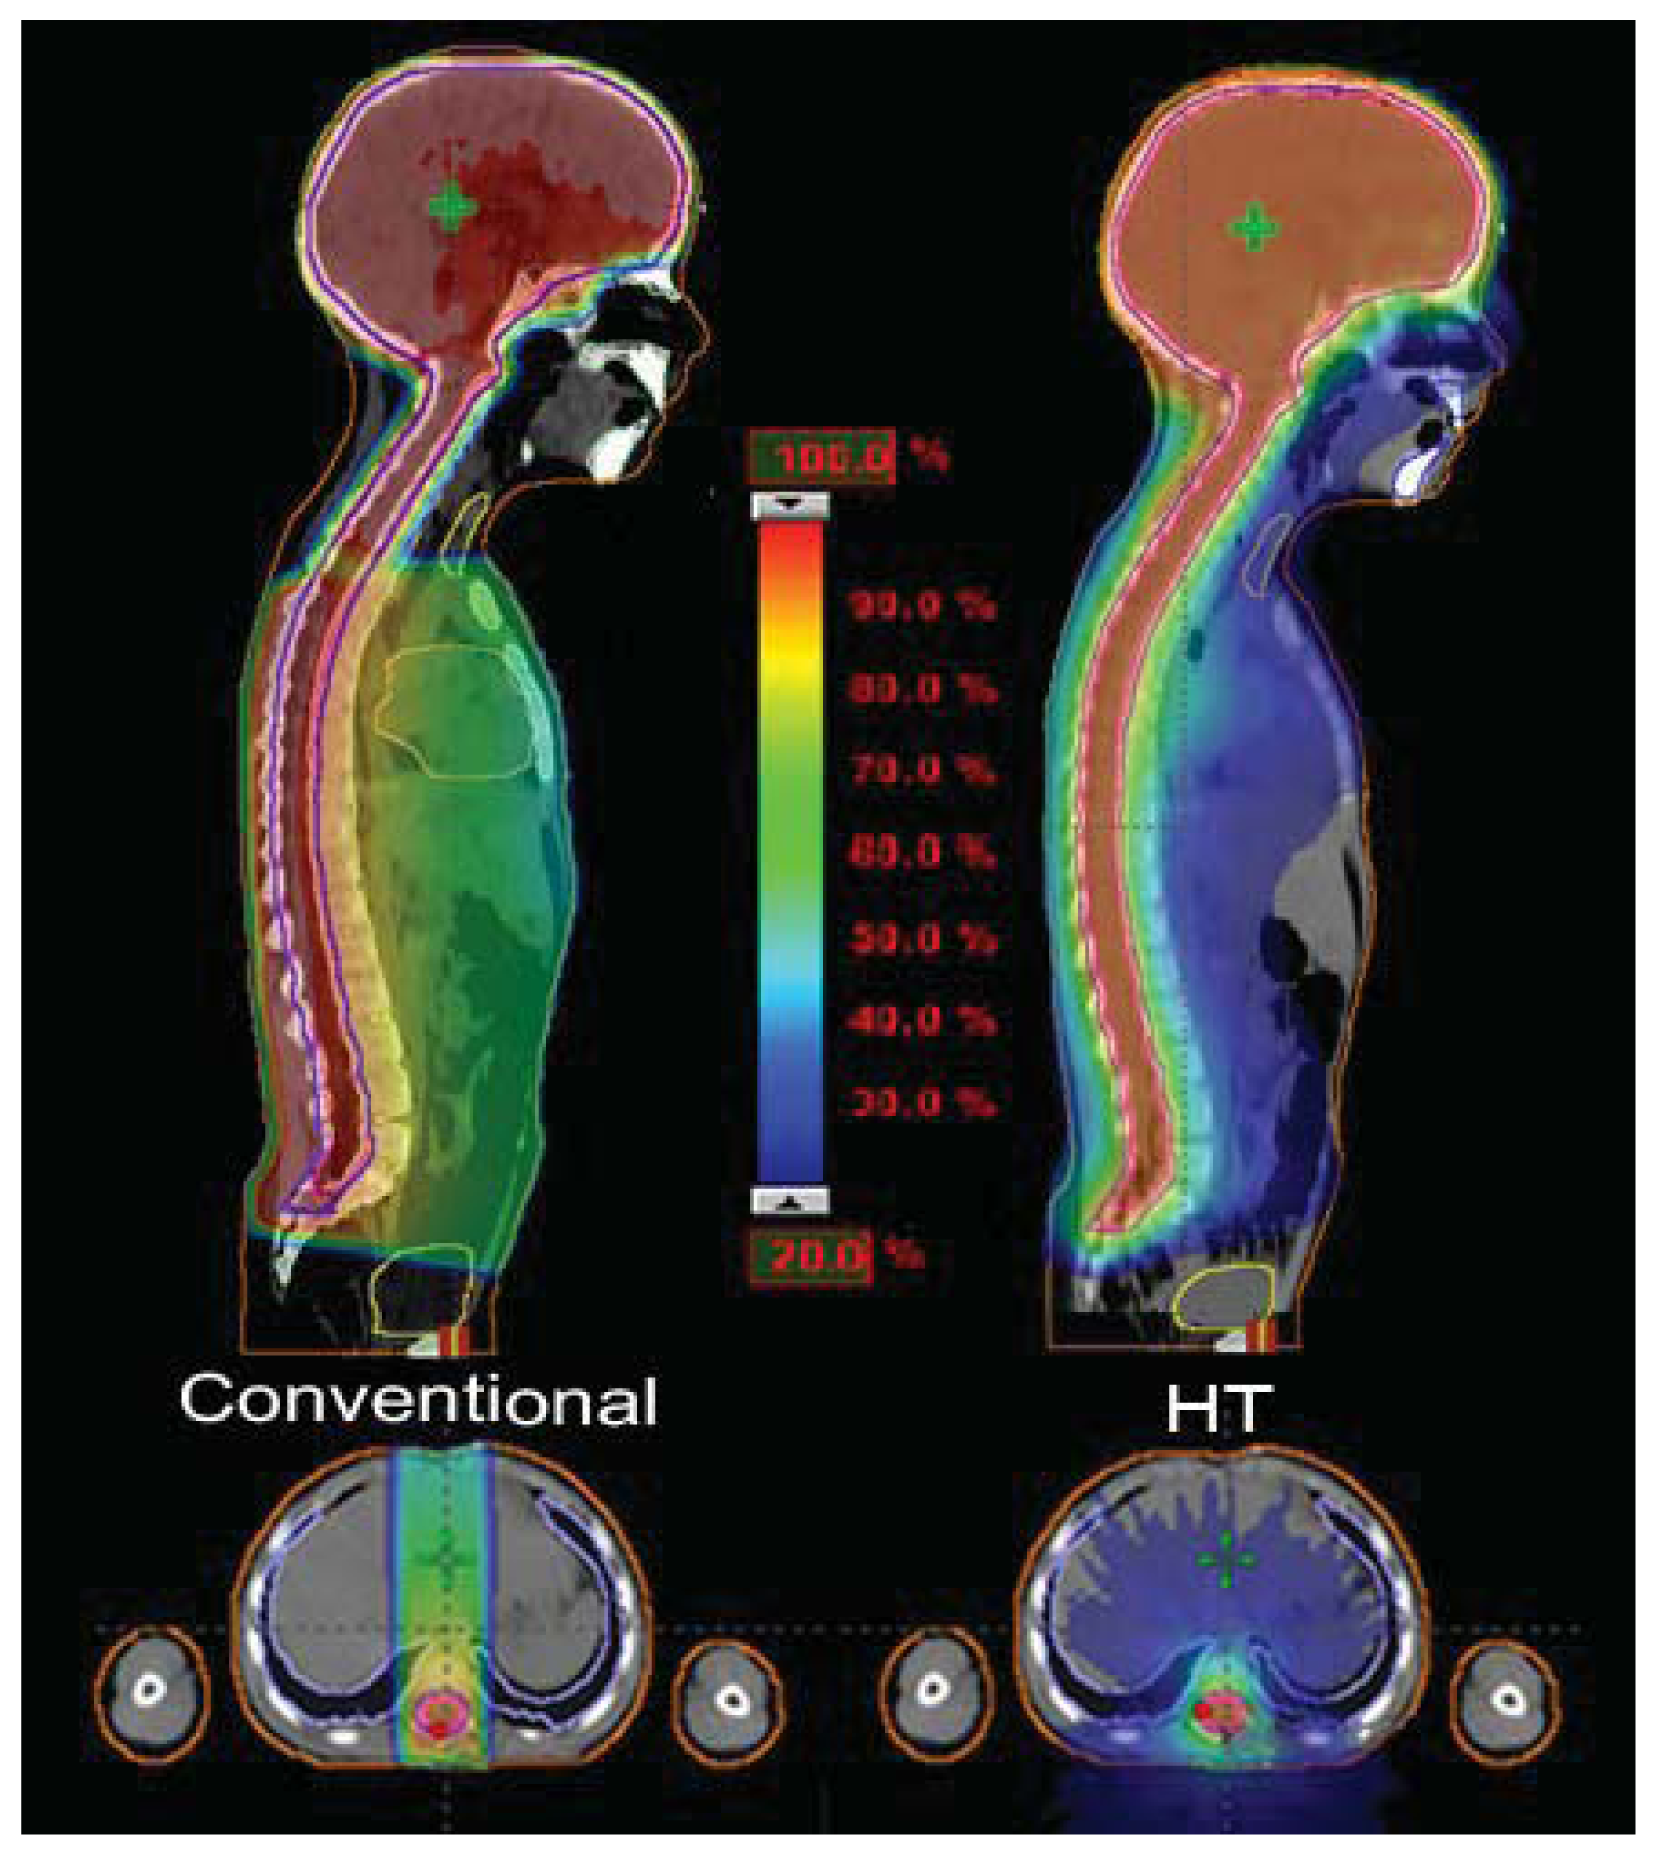

Structures contoured as OARs for the brain patient group were both parotids, teeth, the mandible (including temporo-mandibular joint), the spinal cord, optical structures (optical nerves, chiasm, eyes, lens), the brain, the brain stem, the pituitary gland, temporal lobes, the cochlea, and the thyroid gland. The choice of sparing one organ‘more than another’ is a complex clinical and technical challenge. The use of delivery systems with a very high degree of freedom, such as HT, could permit us to explore the potential of sparing other structures and tissues that normally cannot be efficiently spared with more conventional 3D-CRT or IMRT techniques [9]. Examples of OARs are the cochlea and the pituitary gland in the treatment of the brain. Much importance is given to the prevention of hearing loss as it could compromise the quality of life of these young and very young patients, especially in the workplace and during social relations. Despite its small size (mean volume 0.14 cc), the cochlea is easily identified on CT planning with 3 mm cut [10]. We slightly expanded the anatomic cochlea contour as an OAR to facilitate its preservation from excessive radiation because of its small size. In fact, the value of data resulting from HT planning optimization is not so accurate for OARs whose volumes are lower than 2 cc. Neuroendocrine disturbances in anterior pituitary hormone secretion are common following radiation damage, the severity and frequency of which correlate with the total radiation dose delivered to the hypothalamus-pituitary axis and the time that has elapsed since treatment. Classically, growth hormone (GH) is the most sensitive of the anterior pituitary hormones to irradiation, followed by gonadotrophins, adrenocorticotrophic hormone (ACTH) and thyroid-stimulating hormone (TSH). The somatotrophic axis is the most vulnerable to radiation damage and GH deficiency remains the most frequently seen endocrinopathy. In our example of a 2-year-old male with an atypical teratoid rhabdoid tumor of the quadrigeminal region, the HT plan has been compared with 3D-CRT using no-coplanar fields. The tightly conformal dosimetric characteristics of HT were not advantageous with respect to the cochlea and pituitary gland DVHs. In this case, the relatively small volume of treatment, the regular target volume and the opportunity to choose the entrance fields with CRT, favored applying the latter option (Figure 2). Some patients with brain tumors need CSI and, in this case, HT has a frequent application. In our experience in a 4 year-old-male affected by medulloblastoma treated with HT (Figure 3), an inspection of DVH reveals excellent conformal quality both for CTV brain and spinal cord with better sparing of OARs close to the target [7]. In comparison with conventional techniques, CSI delivered with HT is able to achieve better dose homogeneity and conformality in the target volume. With HT-CSI lower doses are distributed to larger volumes and higher doses to smaller volumes, with higher doses confined to a very small volume. The potential drawback of the low dose bath is that it could have an effect on acute toxicities (e.g., on the lung, on the gastrointestinal tract) and on the total body ID [7].

On the contrary, the total body ID slightly increases in comparison to conventional techniques delivered with linear accelerator. Based on our experience, in 15 children younger than 8 years treated with CSI for different brain tumors, the total body ID showed a difference of about 11% in favor of 3D-CRT-CSI when compared to HT-CSI [12,13]. However, results for ID in CSI vary in the literature. Shi et al., in a single patient study, showed that the HT plan produces lower non tumor ID when compared to the step-and-shoot IMRT plan, and better homogeneity for the spinal PTV [14]. In a comparison between HT and conventional CSI, Penagaricano et al. found an ID 8% higher in two patients, but 2% lower in another one [15]. Finally, Sharma et al., in a dosimetric study in 4 pediatric and adolescent patients, reported that HT-CSI was able to reduce the ID in 4 of the 10 analyzed OARs (heart, thyroid, liver and esophagus) when compared to 3D-CRT-CSI. The authors focused their study on OARs, but the total body ID was not reported [16].

Hypothyroidism is another common late effect, not only after CSI, but also in neck/mediastinum irradiation. The frequency of compensated hypothyroidism is reportedly as high as 43.8% among adults and 80% among children after neck irradiation. Thyroid dysfunction may develop from a few months to several years after patients have completed their RT. In children with chronic diseases, or given lengthy anti-neoplastic treatments, recurrent or persistent endocrine disorders may have a negative effect on the growth and the development of a child into adulthood [17]. With regard to the thyroid in conventional 3D CSI, the upper part of the gland received, with two cranial opposed fields, about 20% of the delivered dose and the lower part, with direct posterior field, between 50% and 70% of the delivered dose. In the HT plans, 90% of the thyroid volume received lower than 23% of the delivered dose (Figure 3).